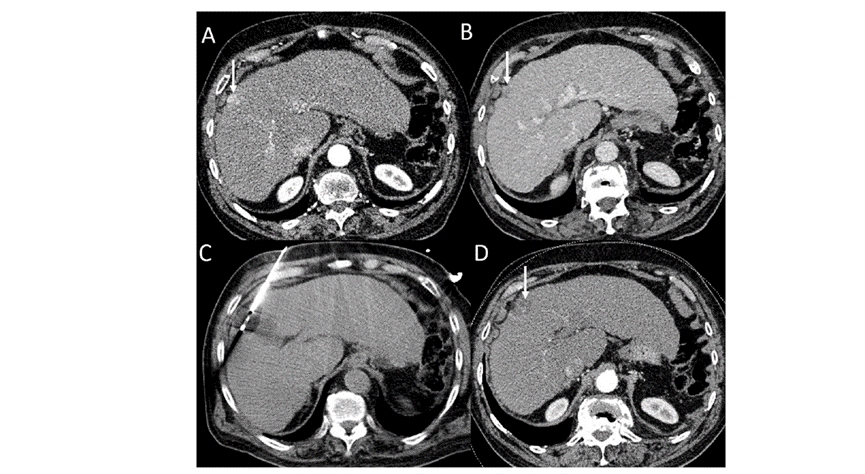

CT引導的冷凍消融

手術(shù)前后實(shí)驗室檢查結果的變化